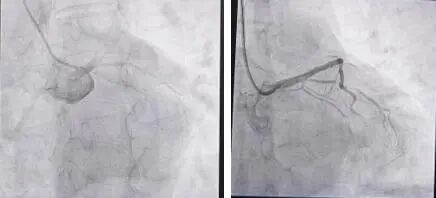

经过一系列检查,急诊科医生判断赵先生是急性侧壁+前间壁+前壁心肌梗死、心源性休克,于是立即联系心内科副主任医师陈晨,准备急诊手术。此时的赵先生已处于心源性休克状态,病情凶险。急诊冠脉造影结果显示,他的左主干血管末端完全闭塞,相当于心脏的主供血管被彻底堵死,还合并有心房颤动。“前降支闭塞导致的大面积前壁心肌梗死,合并新发房颤后,心源性休克、恶性心律失常甚至猝死的风险会成倍增加。”陈晨表示。

赵先生的救治过程远比想象中曲折。首根导丝尝试多次均未能通过闭塞病变,最终在微导管辅助下穿过闭塞部位。但急性血栓堵塞了血管,球囊扩张后血管仍无血流通过,陈晨立即采取刺破球囊冠脉内给药、血栓抽吸等一系列操作,终于看到远端血管显影,随后在前降支近段植入支架,复查显示整个血管血流通畅,第一步救援宣告成功。

左边为救治前的血管造影,右边为救治后的血管造影